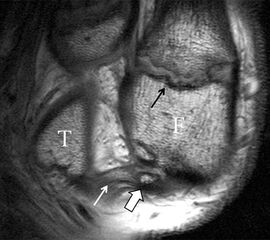

Ligamentum fibulotalare anterius (LFTA)

Das Ligamentum fibulotalare anterius entspricht einer bifaszikulären Struktur (Abb. 2 a) mit interponierendem fibrovaskulärem Gewebe (S. K. Sarrafian (ed). 2003). Es gibt jedoch Variationen der Ligamentanatomie. In 55% liegt das LFTA als bifaszikuläres Band (Abb. 2 a), in 9% als monofaszikuläre Bandstruktur (Abb. 2 b) und in 36% als multifaszikuläre, striäre Variante (Abb. 2 c) vor 3.

Das LFTA verbindet die antero-inferiore Fibulaspitze mit dem Processus lateralis tali und inseriert hier an einem oder zwei kleinen Tuberkeln 3. Der in Neutralposition horizontale Verlauf erleichtert die kernspintomographische Darstellung in dieser Standardebene. Das LFTA weist durchschnittlich eine Breite von knapp über 2 mm auf 4. Somit sind bei einer Routinedarstellung in 3 mm Schichtdicke Anschnittsphänomene, die die Diagnostik erschweren, regelmäßig anzutreffen. Dementsprechend sind auch die ligamentären Subfaszikel nicht zu differenzieren. In koronarer Darstellung ist dies aufgrund der hohen Auflösung in der Schichtebene jedoch möglich (Abb. 2 a-c), wobei hier wiederum eine Integritätsbeurteilung des Bandes erschwert ist. Unter Verwendung hochauflösender Techniken im Millimeterbereich (Schichtdicke) sind hingegen auch in der axialen Ebene die subfaszikulären Strukturen zu beurteilen (Abb. 3).